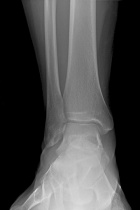

22 year old male with h/o ankle injury presents with progressively increasing pain in right ankle

Zoom image: Radiological image Radiological image.